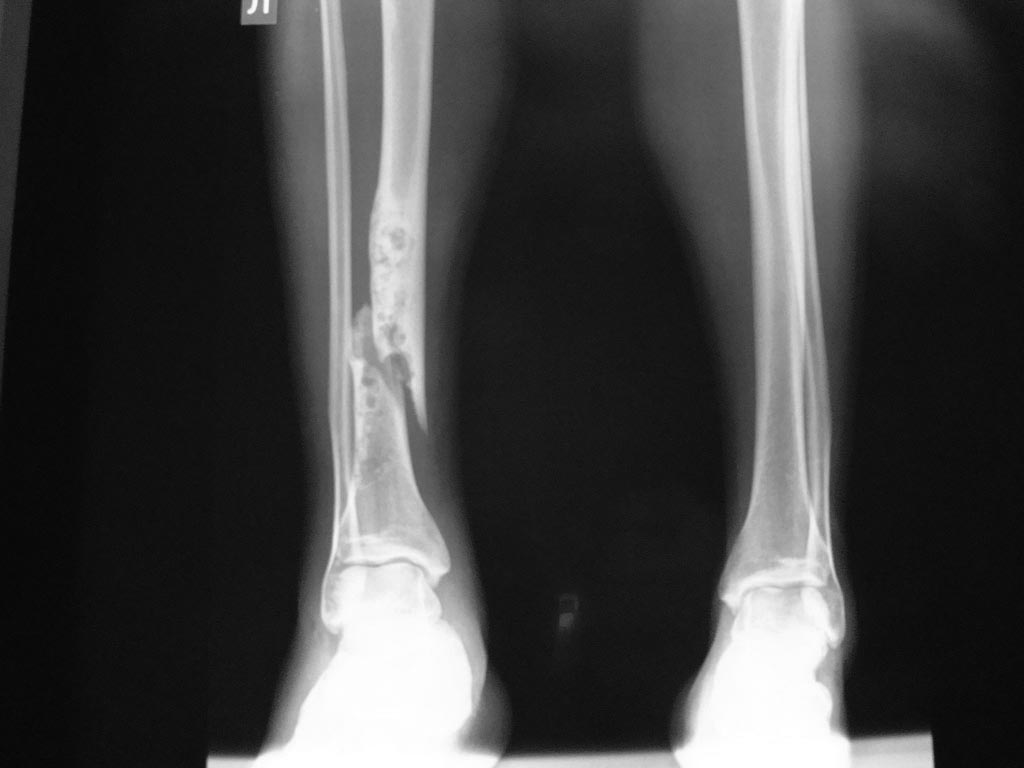

Может все-таки не патологический?

И опять же перелом не голени, а только малоберцовой кости, судя по линии излома- механизм- ротация.

Дополнение к предыдущему посту- у меня открылся только снимок с в/з голени, теперь "проявилась" и н/з- спасибо модератору.

Я - за фиброзную дисплазию.Лечение оперативное.

напоминает перелом на фоне абсцесса Броди, для него характерны из анамнеза длительные ночные боли и при движении , характерно для мужчин молодого возраста, чаще всего бывает на большеберцовой кости(80 % случаев), единственное что не характерно это остеопороз около кости который виден у данного больного( чаще перифокальный остеосклероз). а что из исследований доступно: пункия с гистологией, КТ, УЗИ, инфракрасная термография.

Здравствуйте, Александр! по представленным данным на первое место в диф.ряду я бы поставил фиброзную дисплазию. более точно можно будет сказать оценив структуру по КТ - если возможно, присылайте больного на обследование (живая очередь, с 10-00 до 14-00, 1476руб., я делаю в любой вторник и пятницу, только завтра не могу, будут проф.работы на КТ, справки по тел.371-48-11), или присылайте диск с данными КТ

В диагностике опухоли локализация и возраст пациента являеются важными. Из всех патологий большеберцевой фиброзная дисплазия более близка к представленной картине, но в третьей декаде жизни встречается очень редко. Остеофиброзную дисплазию многие онкологи считают проявлением регрессивной фазы адамантиномы, которая, в отличие от фиброзной дисплазии, является злокачественной формой опухоли большеберцовой кости.

Независимо от диагноза лечебная тактика состоит в сегментарной остеотомии большеберцовой и замещении кости. Замена доброкачественной опухоли отличается от постравматических дефектов, где нескомпрометированные мягкие ткани позволяют выбрать более агрессивные пластические материалы, чем после травмы. Вместо долгих ожидании титановый кейдж с интрамедуллярной фиксацией или аллографт, кроме экономии времени, дадут предсказуемый результат.

Дополнительные исследования помогут выбрать оптимальный вариант лечения, например, МРТ покажет характер опухоли, а КТ срезы позволяют узнать уровень резекции, но окончательный диагноз установит только биопсия! При подтвердении добракачественного варианта тогда подойдет кейдж с аутокостью внутри.